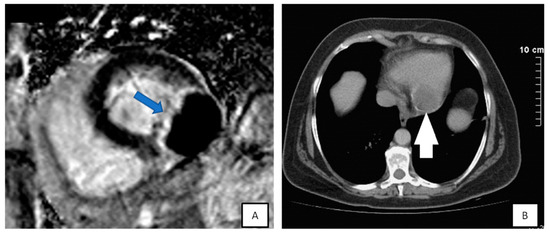

3.4. Cardiac Magnetic Resonance

- Tissue characterization on T1–T2 weighted images:

- High T1 signal intensity is also seen in lipomas. These masses and other lipomatoses can be recognized with fat suppression techniques (Figure 11).

- Early gadolinium enhancement (EGE) which identifies thrombus from the adjacent hypokinetic cardiac wall.

- Late gadolinium enhancement (LGE) that is ideal for fibrosis and necrosis identification.